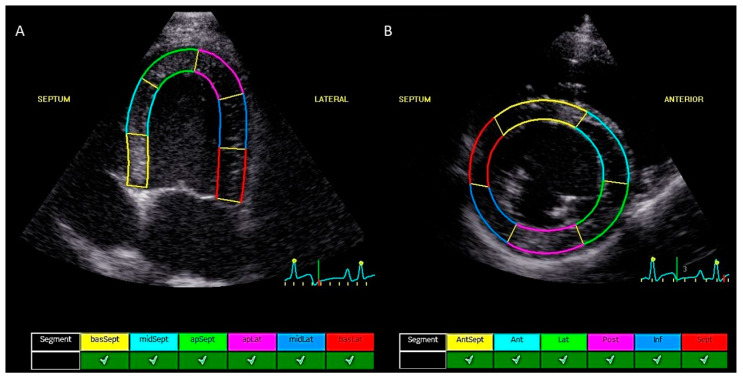

Combretastatin A4-phosphate (CA4P)是一种血管破坏剂,最近被描述用于治疗犬实体肿瘤。传统的超声心动图和脉冲波组织多普勒成像并没有显示狗的心脏毒性,然而,评估接受心脏毒性化疗的人类心肌损伤的金标准是二维斑点跟踪超声心动图。目前的研究评估了单剂量CA4P对狗的心脏毒性作用,使用峰值收缩应变测量和这些测量的可变性。回顾性分析了7只健康小猎犬和5只接受CA4P治疗的犬癌患者的超声心动图检查结果。测定CA4P给药前和给药后24 h的收缩区域纵向应变峰值(LSt)、收缩区域周向应变峰值(CSt)和收缩区域径向应变峰值(RSt)。将峰值收缩应变测量值与血清心肌肌钙蛋白I (cTnI)进行比较。为了量化观察者内部和观察者之间的测量变异性,选择了7个超声心动图检查,每个应变参数由3个观察者连续3天测量。CA4P治疗后,LSt和CSt的中位数分别下降了21.8% (p = 0.0005)和12.3% (p = 0.002),而RSt的中位数差异无统计学意义(p = 0.70)。LSt降低与血清cTnI值升高相关(Spearman ρ = -0.64, p = 0.02)。LSt、CSt和RSt的观察者内变异系数(CV)分别为9%、4%和13%,而相应的观察者间变异系数(CV)分别为11%、12%和20%。我们的研究结果表明,局部峰值收缩应变测量可能有助于血管破坏剂引起的心脏毒性的早期检测,并且LSt可能有希望用于犬癌症患者的随访。

Combretastatin A4-phosphate (CA4P) is a vascular disrupting agent that was recently described for the treatment of solid canine tumors. Conventional echocardiography and pulsed wave tissue Doppler imaging did not reveal cardiotoxicity in dogs, however, the gold standard for assessing myocardial damage in humans receiving cardiotoxic chemotherapeutics is two-dimensional speckle-tracking echocardiography. The current study evaluated the cardiotoxic effect of a single dose of CA4P in dogs using peak systolic strain measurements and the variability of these measurements. Echocardiographic examinations of seven healthy beagles and five canine cancer patients that received CA4P were retrospectively reviewed. Peak systolic regional longitudinal strain (LSt), peak systolic regional circumferential strain (CSt), and peak systolic regional radial strain (RSt) were measured before and 24 h after administration of CA4P. Peak systolic strain measurements were compared to serum cardiac troponin I (cTnI). To quantify intra- and inter-observer measurement variability, seven echocardiographic examinations were selected and each strain parameter was measured by three observers on three consecutive days. After CA4P administration, the median LSt and CSt values decreased by 21.8% (p = 0.0005) and 12.3% (p = 0.002), respectively, whereas the median RSt values were not significantly different (p = 0.70). The decrease in LSt was correlated with increased serum cTnI values (Spearman rho = -0.64, p = 0.02). The intra-observer coefficients of variation (CV) were 9%, 4%, and 13% for LSt, CSt, and RSt, respectively, while the corresponding interobserver CVs were 11%, 12%, and 20%. Our results suggest that regional peak systolic strain measurements may be useful for the early detection of cardiotoxicity that is caused by vascular disrupting agents and that LSt may be promising for the follow-up of canine cancer patients.